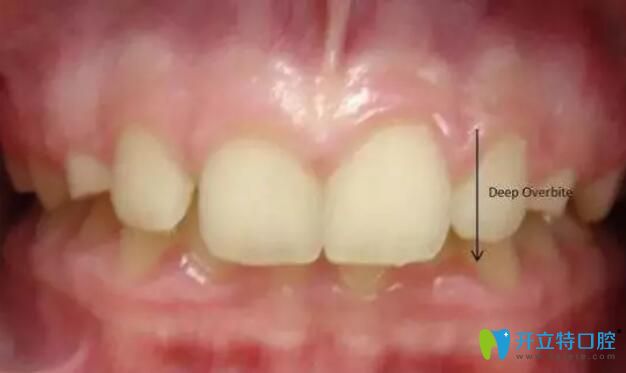

科普:深覆合骨性和牙性的區(qū)別并附骨性和牙性的矯正方法

牙齒排列不整齊畸形其實(shí)有很多表現(xiàn),比如上牙包裹下牙太多的深覆合,深覆合又有骨性和牙性,那么到底怎么區(qū)別,分別怎么矯正,以下科普讓你清清楚楚。